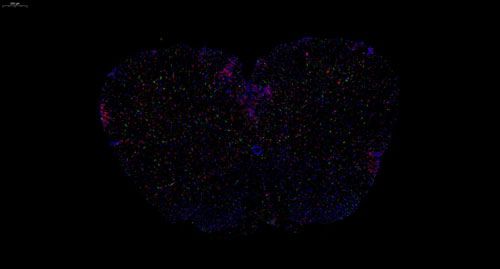

小鼠脊髓 普通切片扫描(荧光双标 三色)